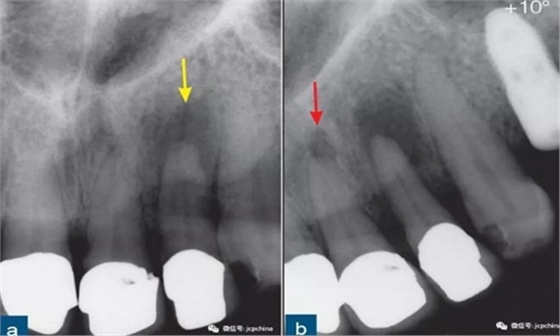

第一張根尖片22牙(黃色箭頭)的根尖周透射影清晰可見(jiàn)。第二張根尖片(水平遠(yuǎn)中方向偏移10°)顯示21牙的根尖周“透射影”(紅色箭頭)。此“透射影”實(shí)際上是切牙孔,該解剖噪點(diǎn)和根尖周透射影的表現(xiàn)類似。

所以,經(jīng)驗(yàn)不足的臨床醫(yī)生很容易誤診。